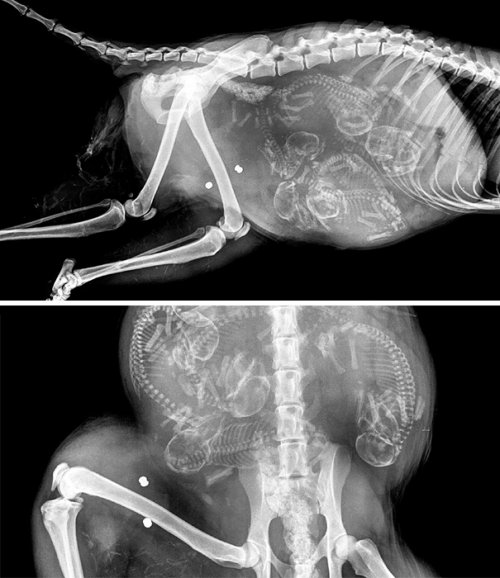

Итак, как выглядят рентгеновские снимки беременных животных:

собака